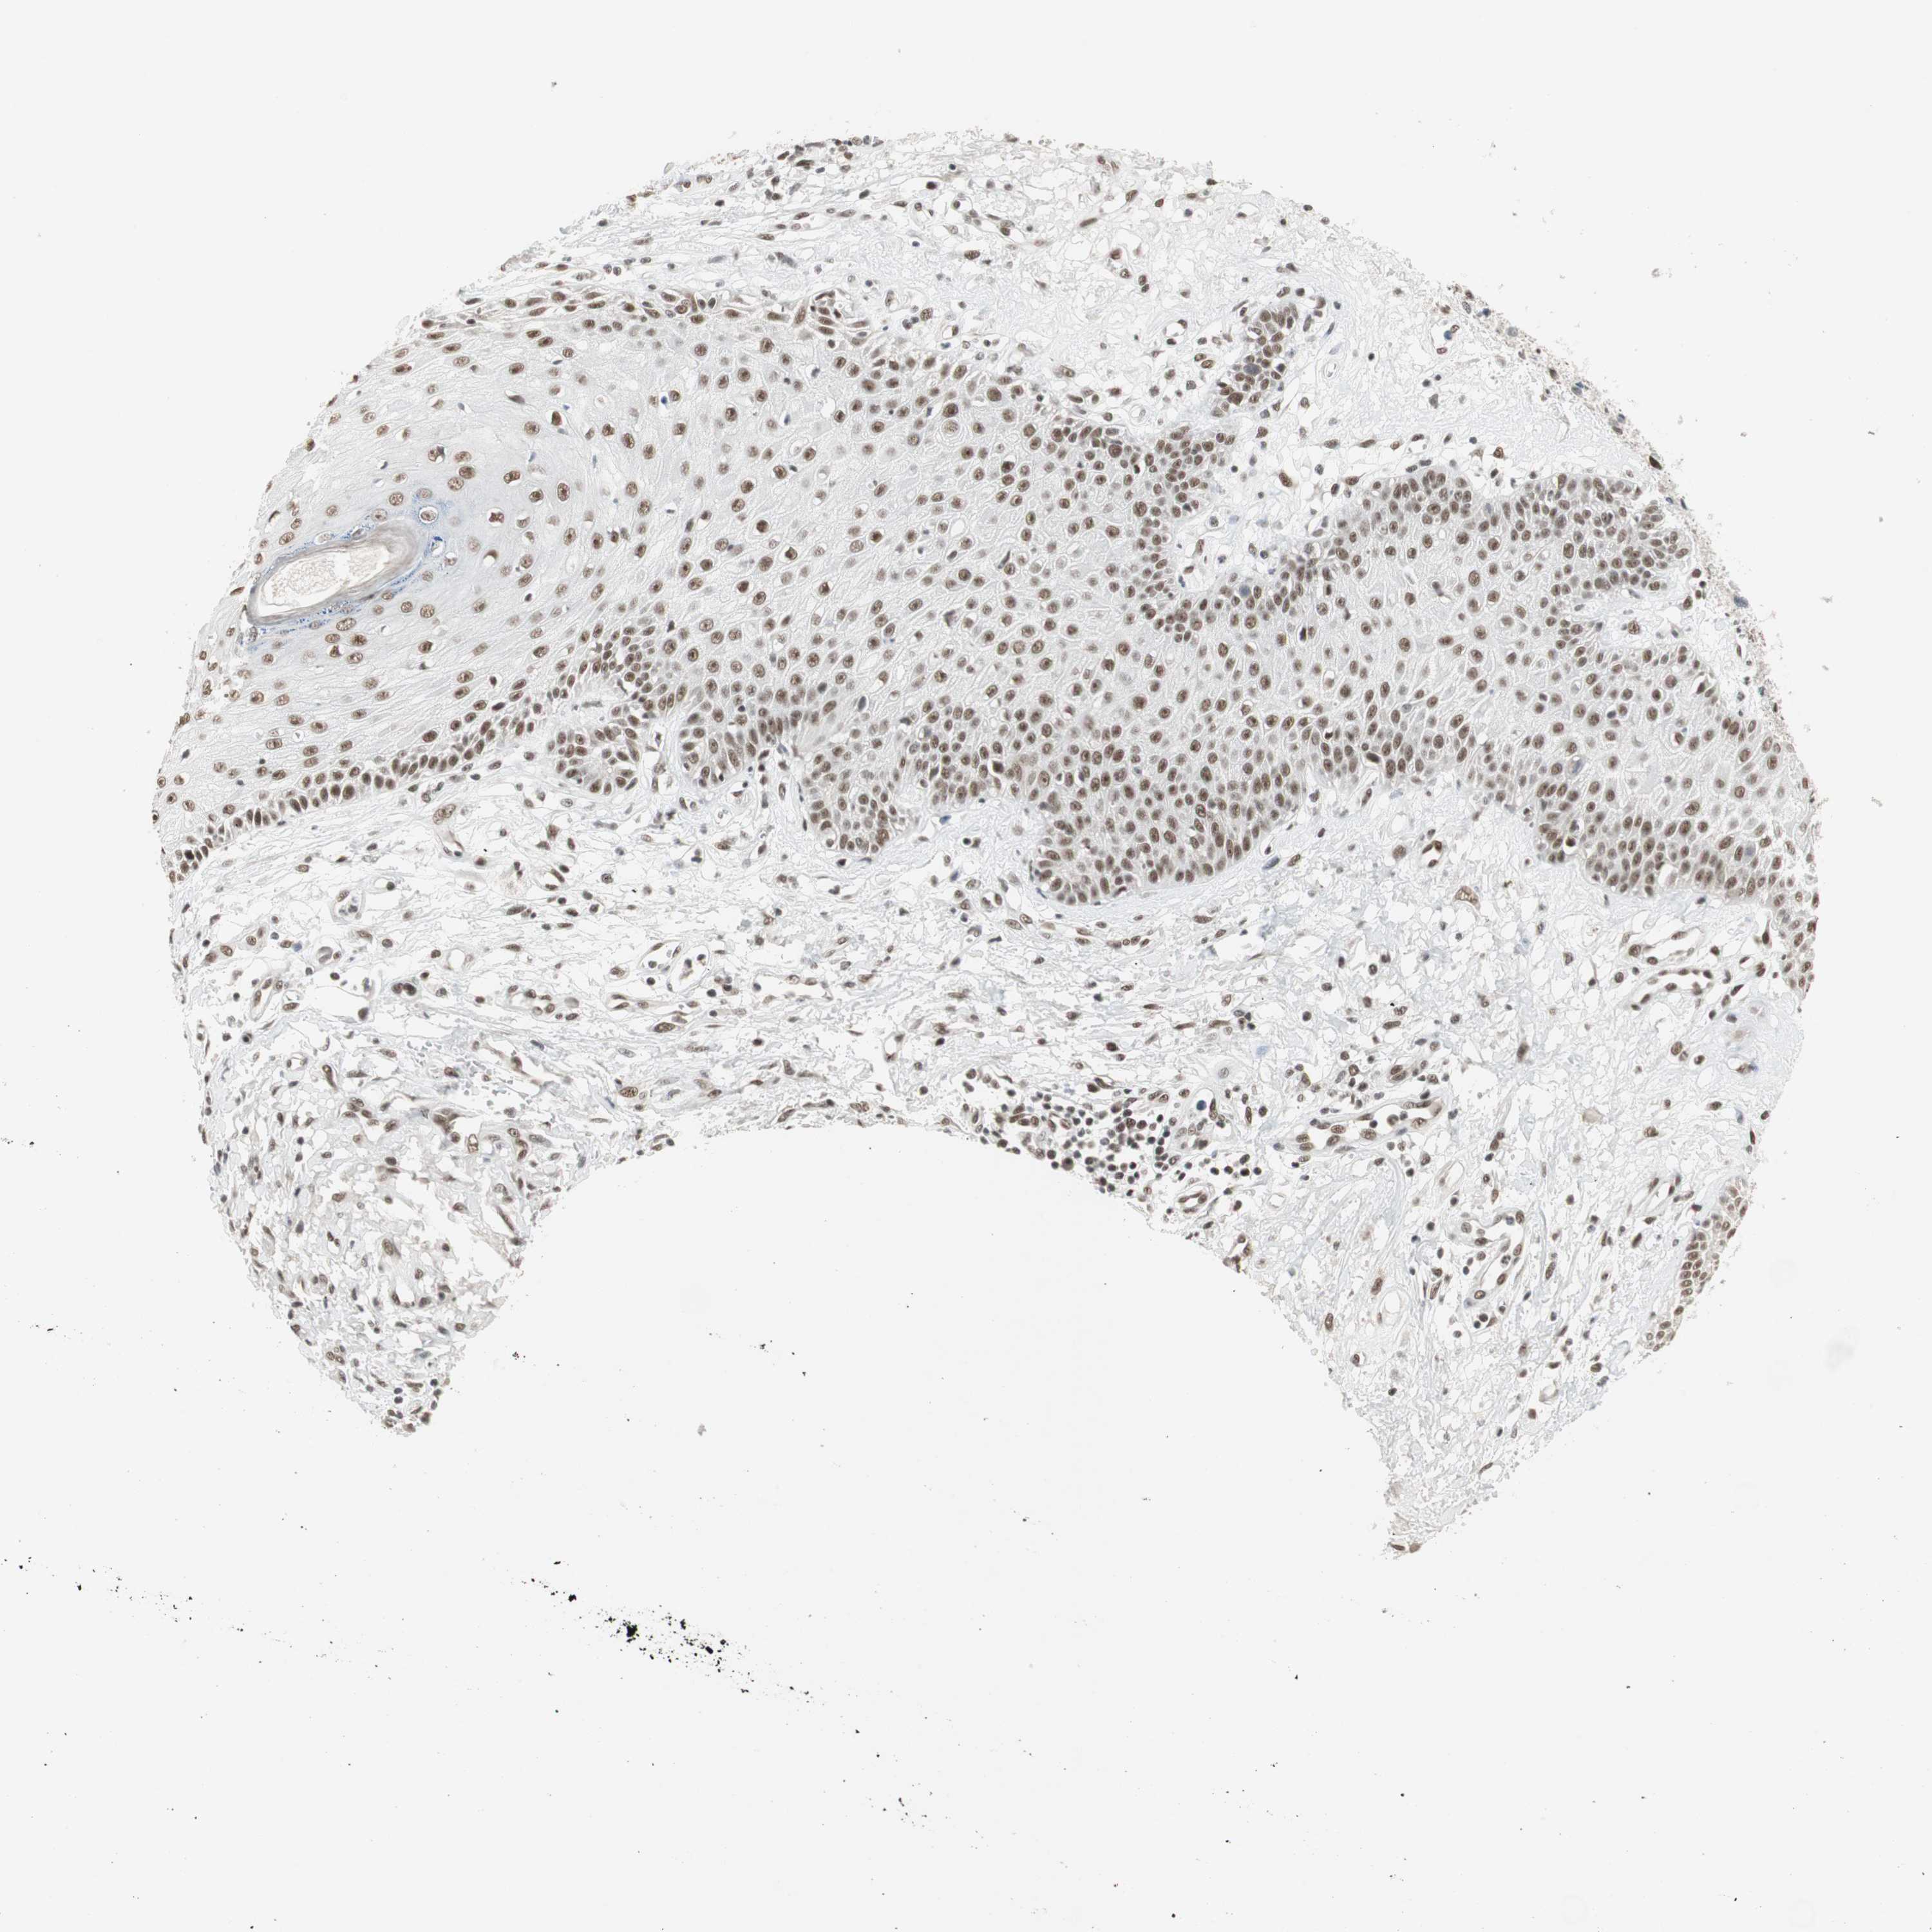

SKIN CANCER - Protein expressioni

A mouse-over function shows sample information and annotation data. Click on an image to view it in a full screen mode. Samples can be filtered based on level of antibody staining by selecting one or several of the following categories: high, medium, low and not detected. The assay and annotation is described here.

Antibody stainingi

Antibody staining in the annotated cell types in the current human tissue is reported as not detected, low, medium, or high, based on conventional immunohistochemistry profiling in selected tissues. This score is based on the combination of the staining intensity and fraction of stained cells.

Each image is clickable and will lead to virtual microscopy that enables deeper exploration of all samples and also displays staining intensity scores, fraction scores and subcellular localization as well as patient and tissue information for each sample.

Antibody CAB079947

Squamous cell carcinoma, metastatic, NOS